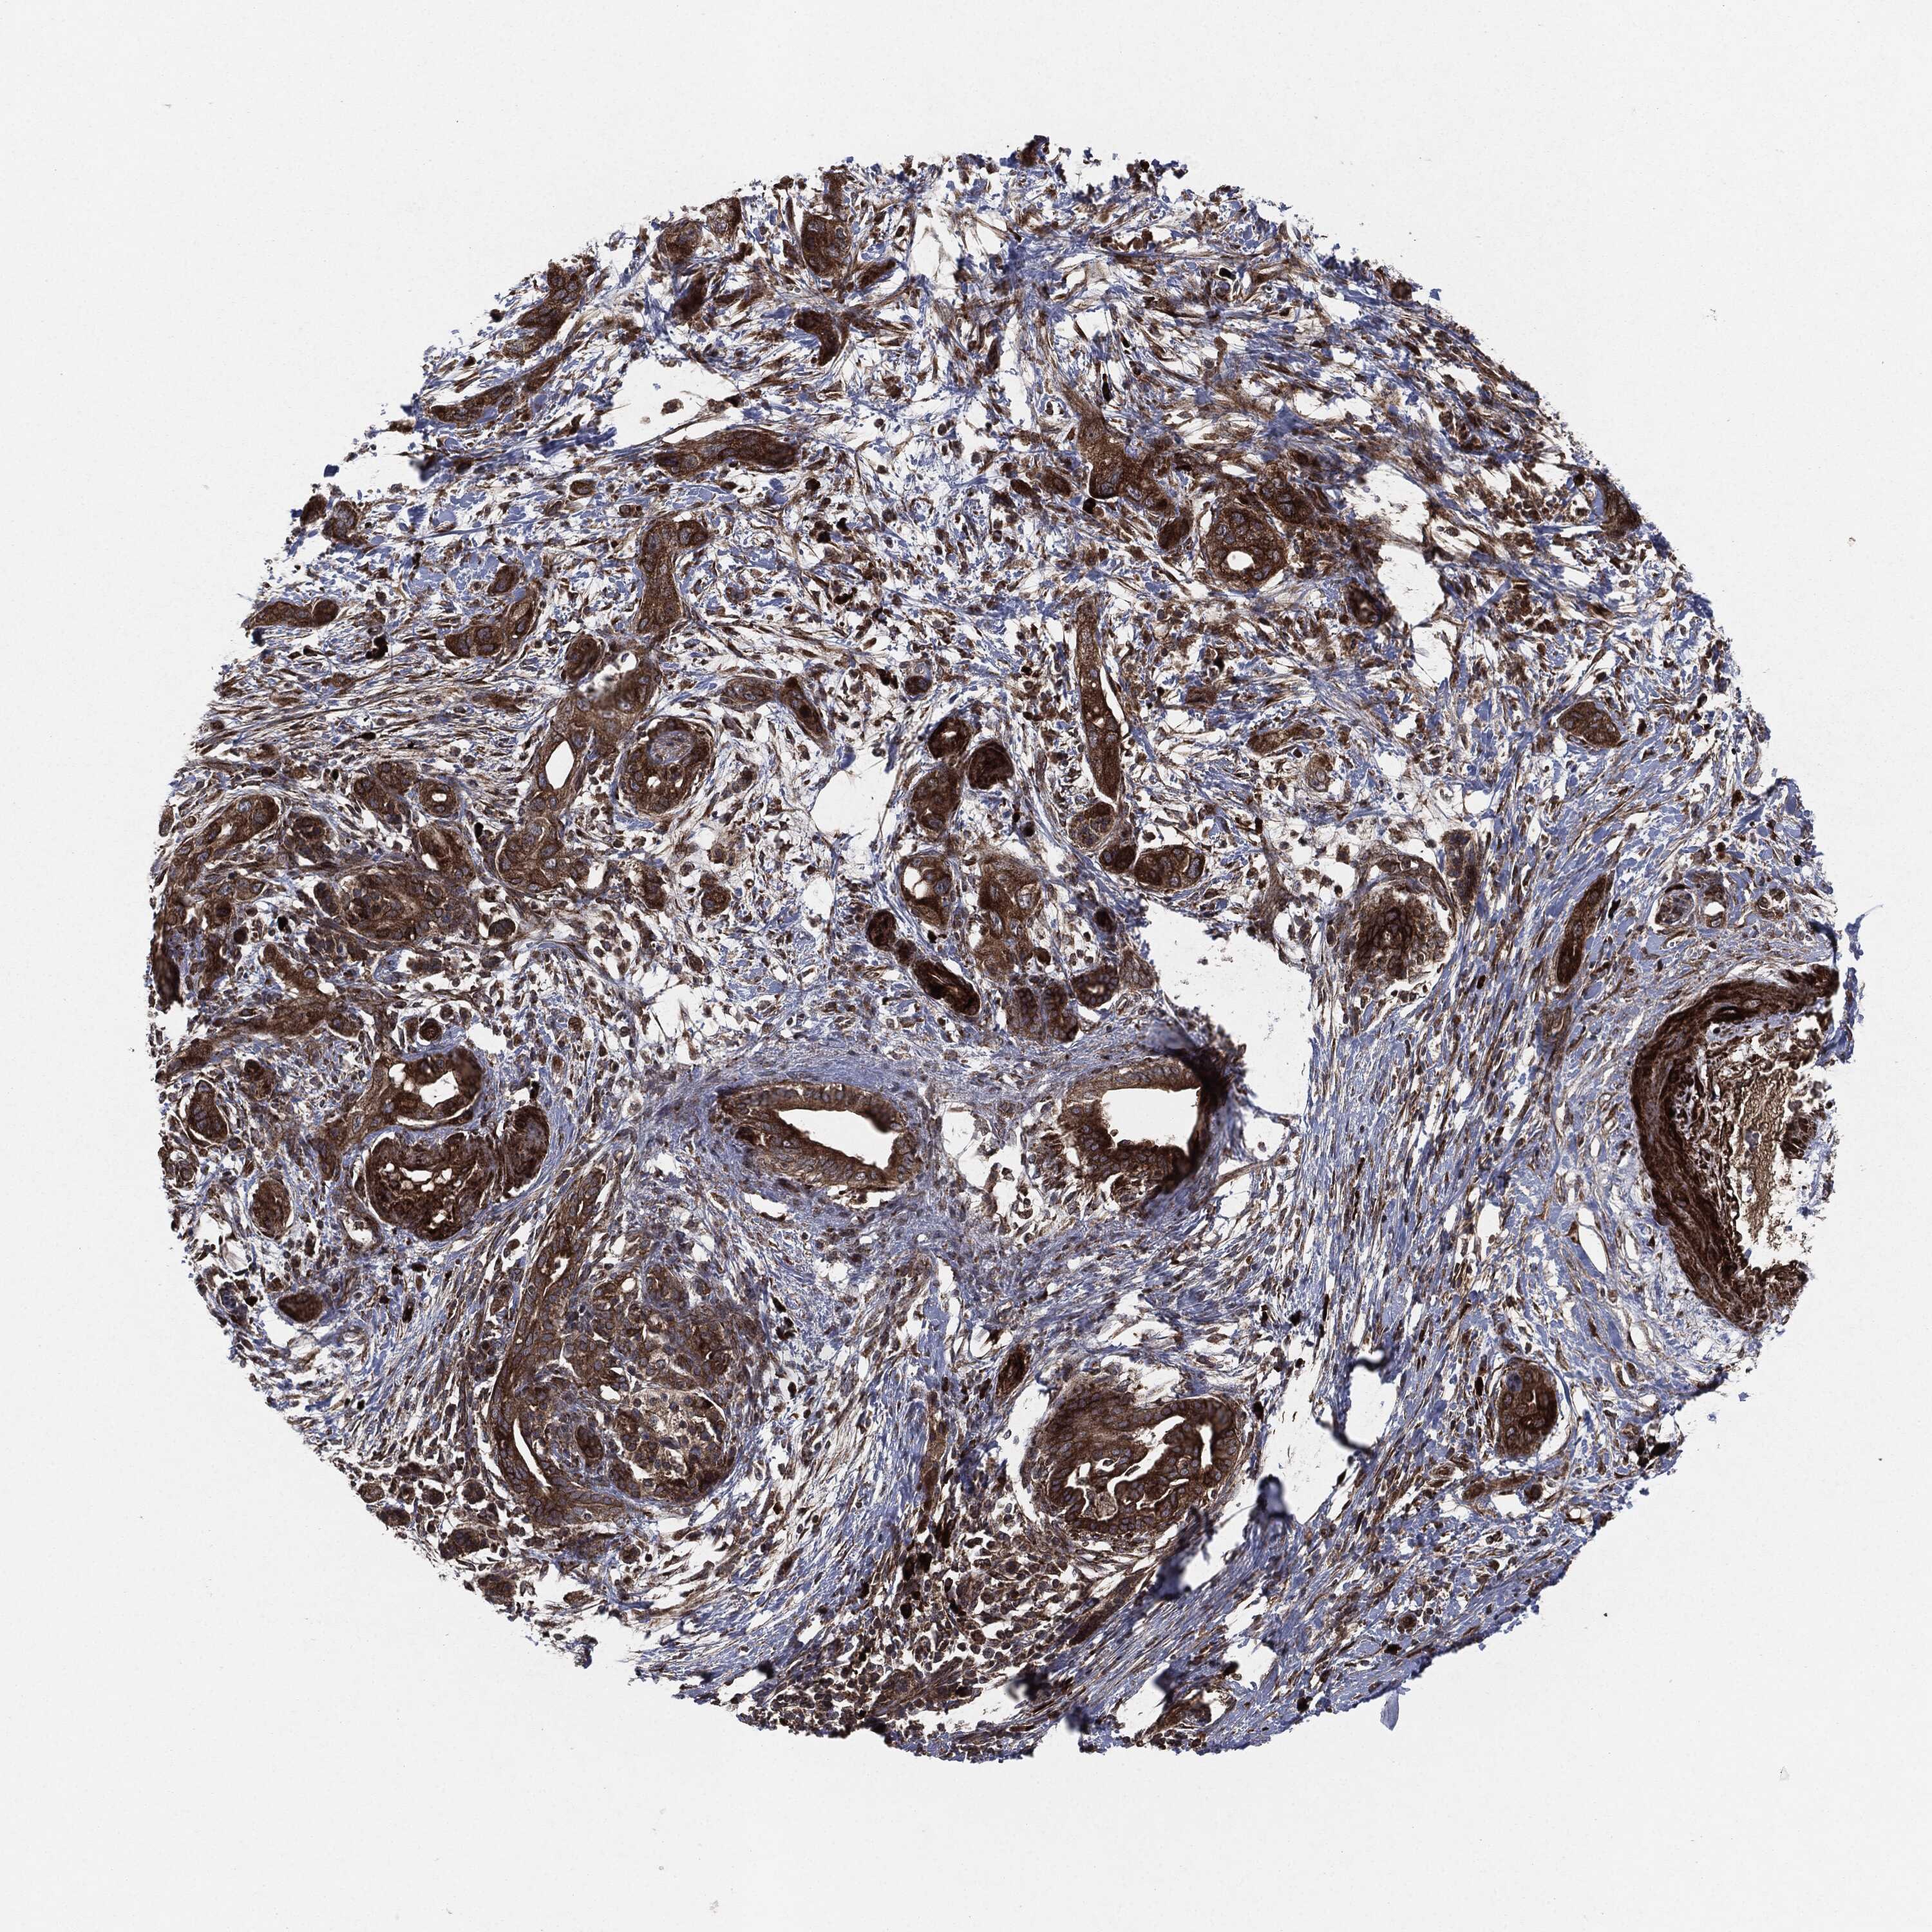

PANCREATIC CANCER - Protein expressioni

A mouse-over function shows sample information and annotation data. Click on an image to view it in a full screen mode. Samples can be filtered based on level of antibody staining by selecting one or several of the following categories: high, medium, low and not detected. The assay and annotation is described here.

Note that samples used for immunohistochemistry by the Human Protein Atlas do not correspond to samples in the TCGA dataset.

Antibody stainingi

Antibody staining in the annotated cell types in the current human tissue is reported as not detected, low, medium, or high, based on conventional immunohistochemistry profiling in selected tissues. This score is based on the combination of the staining intensity and fraction of stained cells.

Each image is clickable and will lead to virtual microscopy that enables deeper exploration of all samples and also displays staining intensity scores, fraction scores and subcellular localization as well as patient and tissue information for each sample.

Antibody HPA002640

Antibody CAB019291

Antibody CAB080384

Staining

High

Medium

Low

Not detected

Intensity

Strong

Moderate

Weak

Negative

Quantity

>75%

75%-25%

<25%

None

Location

Nuclear

Cytoplasmic/membranous

Cytoplasmic/membranous,nuclear

Adenocarcinoma, NOS

Adenocarcinoma, metastatic, NOS